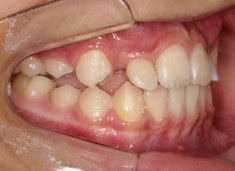

治療開始時

FX(フェイシャルアキシス)は85度なので東洋人の平均値に近く、下顎が前方に過剰成長するリスクは強くはありません。

しかしやはり上顎は劣成長で、下顎が優位な状態ではあります。

上下顎のギャップはありますが、顔面自体の幅径は良好な値を示していますので、スペース不足は拡大することによって解決できポテンシャルはあると考えられます。

左右の非対称もさほど強くありません。